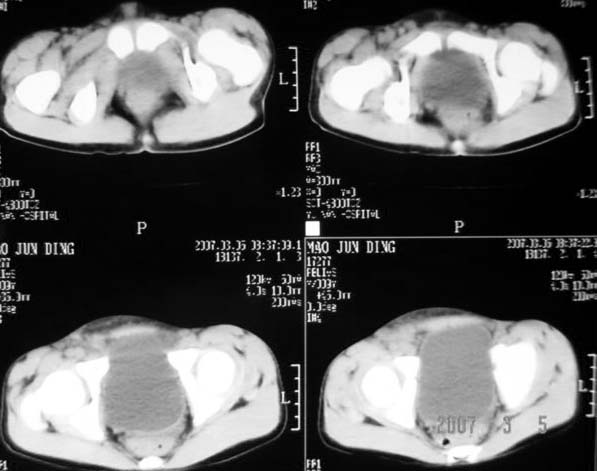

以下是引用dyqct在2007-3-5 10:28:00的发言:[br]右髂窝肿块。[br][br][br][br]